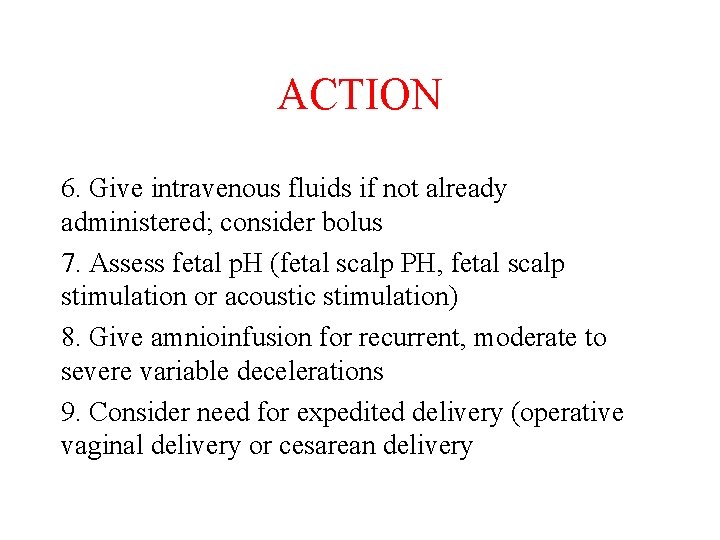

ACTION 6. Give intravenous fluids if not already administered; consider bolus 7. Assess fetal p. H (fetal scalp PH, fetal scalp stimulation or acoustic stimulation) 8. Give amnioinfusion for recurrent, moderate to severe variable decelerations 9. Consider need for expedited delivery (operative vaginal delivery or cesarean delivery